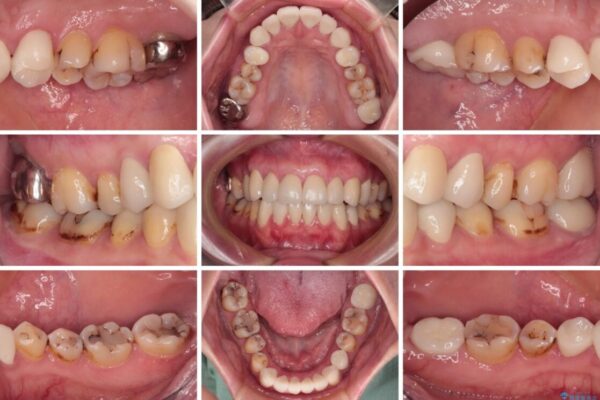

上下前歯や奥歯の虫歯治療を希望して来院された患者様です。

全顎的にむし歯が多く、根管治療の必要な奥歯や、審美的に気になっている前歯を中心にオールセラミッククラウンにて補綴治療を行うこととしました。

上顎前歯は歯肉退縮により歯根が露出していたため、事前に歯肉移植術により根面被覆を行い、その後にオールセラミッククラウンを装着することとしました。

治療前

• むし歯だらけの前歯をオールセラミッククラウンできれいに 治療前画像